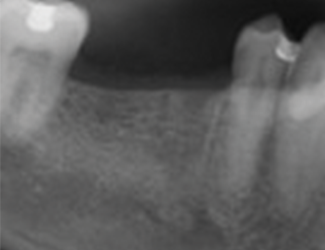

45 år gammel mann som for fem måneder siden gjennomgikk ekstraksjon av tann 45 og 46.

Fem måneder senere ble det observert god tilheling av både ben og bløtvev.

Implantatbehandling ble utført med: Straumann TLX SLActive 4,5 × 10 mm RT i region 45 og Straumann TLC SLActive 4,5 × 10 mm RT i region 46.

Implantatene ble installert med et innsettingsmoment på 45 Ncm. Ved initial ISQ-måling viste begge implantatene en verdi på 79, noe som indikerte god primær stabilitet. Etter åtte ukers tilheling ble implantatene vurdert som stabile for avtrykkstaking før permanent protetisk rehabilitering, med en målt ISQ-verdi på 88.

1. Utgangssituasjon før implantatinstallasjon.